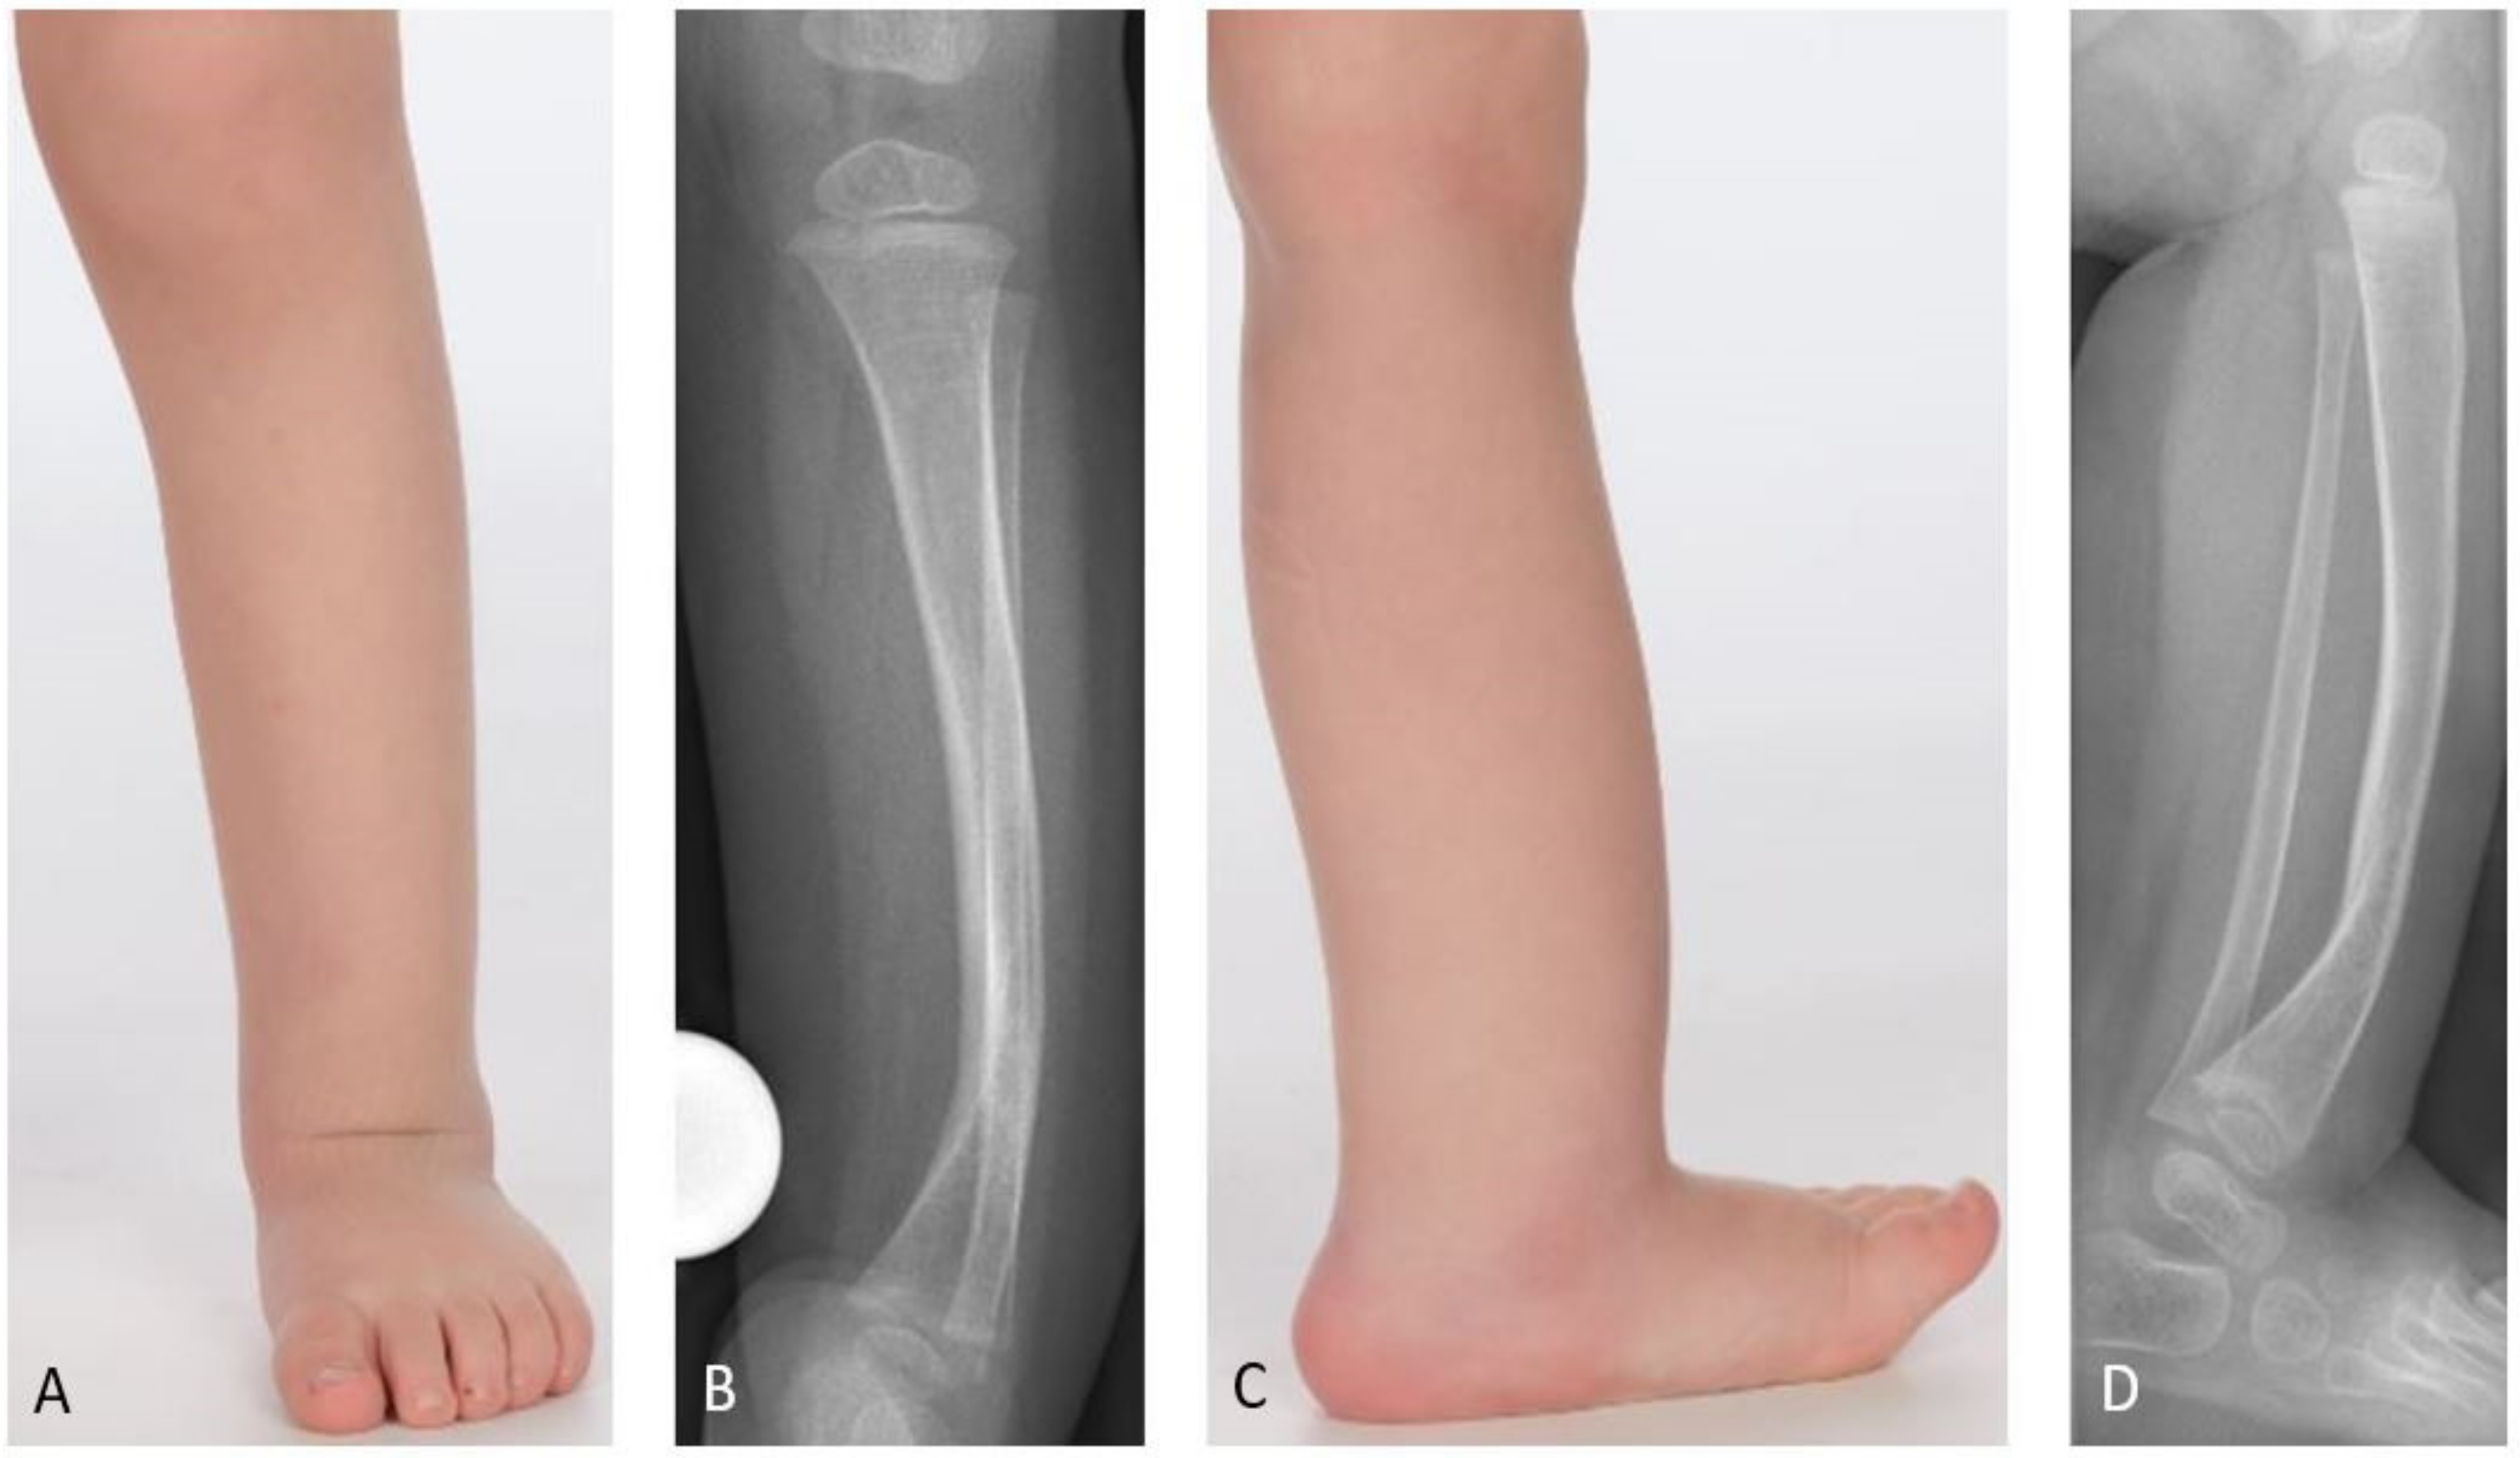

While the Andersen, Boyd, and Crawford classifications are of a rather descriptive nature, the El-Rosasy-Paley classification, which was introduced in 2007, also considers previous unsuccessful surgery [4,9,12,13]. Paley introduced another classification in 2019 which emphasizes the importance of the fibula for treatment and outcome (Figure 2) [8].

In the study cohort CPT was classified according to Paley as follows: Paley type 1 in three patients (12%), type 2A in one patient (4%), type 3 in four patients (15%), type 4A in 16 patients (62%), type 4B in one patient (4%), and type 4C in one patient (4%).

Figure 2. Paley classification for CPT. Type 1: No fractures. Type 2A: No fracture of the tibia; fractured fibula, the fibula is not dislocated. Type 2B: No fracture of the tibia; fractured and proximally migrated fibula. Type 3: Fractured tibia, no fracture of the fibula. Type 4A: Tibia and fibula both fractured. Type 4B: Tibia and fibula both fractured, the fibula is migrated proximally. Type 4C: Bone defect of the tibia, the fibula is migrated proximally [7].